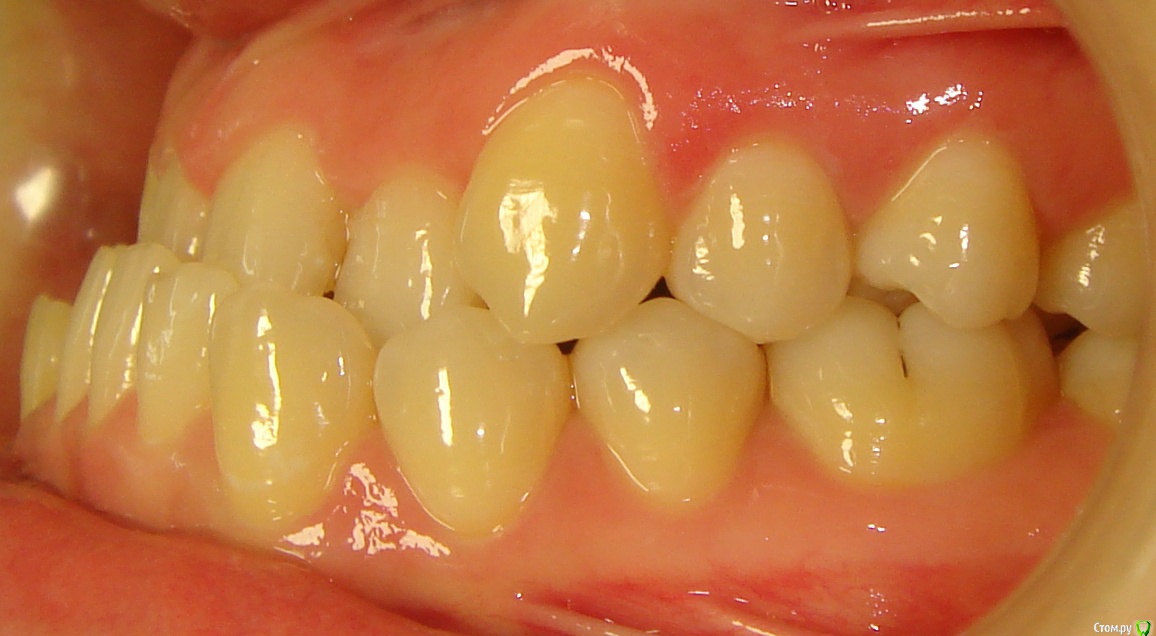

Opdihatop Опубликовано 10 декабря, 2016 Поделиться Опубликовано 10 декабря, 2016 Добрый вечер, коллеги! У меня вопрос к тем, у кого опыта по MEAW больше, чем у меня. Пациентка, 24 года, на данный момент все зубы мудрости удалены, привычная окклюзия по резцам - край в край. Сам процесс я понимаю, но есть несколько нюансов, которые хотелось бы уточнить:1) Нивелировать ли просто фронт в/ч, как книжка пишет (просто поставить дугу и все), или все-таки немного дистализировать боковые участки? С одной стороны простое нивелирование ускорит процесс и облегчит перебрасывание резцов, с другой стороны я опасаюсь чрезмерной протрузии из-за выравнивания дистопированных клыков; но при этом дистализация усугубит 3-й класс.2)Какой высоты делать окклюзионные накладки, в книжке они минимальные, а мне как то хочется побольше, чтобы резцы разомкнуть почти край в край, но не испортит ли это биомеханику?Буду очень благодарен вам за помощь! Ссылка на комментарий

Opdihatop Опубликовано 10 декабря, 2016 Автор Поделиться Опубликовано 10 декабря, 2016 P.S.: на хирургию пациентка согласна, но только, если мультилуп не сработает. Ссылка на комментарий